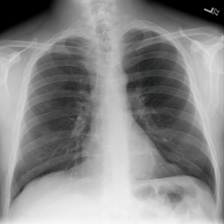

4.7.2 Activation Response Maps

As shown in Fig. 9, given the text lungs, we can find that the activation maps can accurately highlight the target regions. Therefore, we can achieve a higher performance on the downstream tasks. However, the activation maps are imperfect, as the background regions are also highlighted.